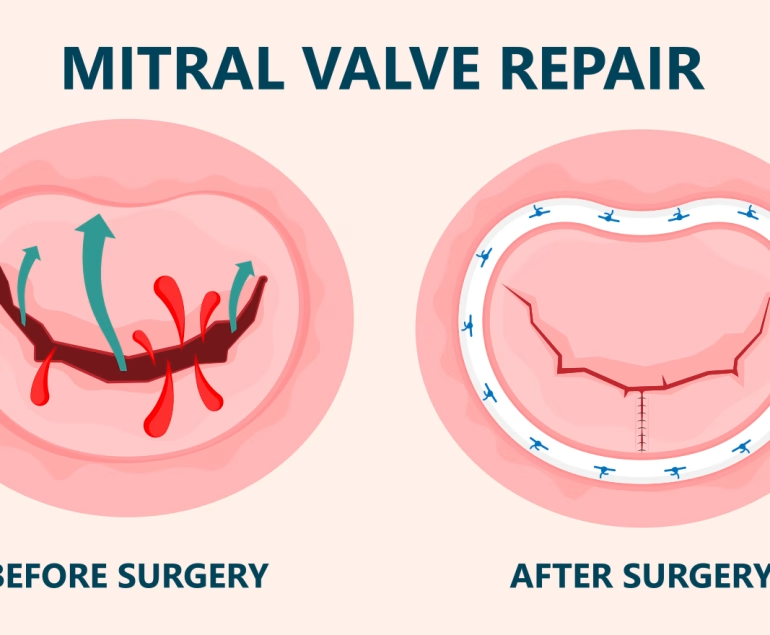

The valve between the left atrium and left ventricle of the heart is called the mitral valve. Mitral stenosis can be defined as the mitral valve opening, which controls blood flow in the heart, being narrower than normal. Mitral stenosis restricts the flow of blood from the left atrium to the left ventricle, which pumps blood to the body. Blood that is prevented from passing into the left ventricle accumulates in the left atrium much more than normal. Thus, the left atrium begins to enlarge and arrhythmias occur. If the enlargement of the left atrium continues to increase, arrhythmias called atrial flutter and then atrial fibrillation develop. Atrial fibrillation is important because this arrhythmia disrupts the contraction function of the left atrium, slows blood flow in the left atrium, and ultimately causes blood clots to form within the left atrium. If this clot moves and enters the systemic circulation, embolisms and strokes may occur.

The mitral valve, which ensures the heart functions regularly and oxygenated blood flows to the body, may not perform its function in various conditions. Mitral stenosis is one of the conditions that affect heart function. Stenosis prevents adequate blood flow to the systemic circulation and causes an increase in pulmonary pressure as a result of blood pooling in the lungs.

If such complaints are present, evaluation by a cardiologist is necessary. Early diagnosis allows for intervention before heart and lung function deteriorates, ensuring that normal function is maintained after treatment.